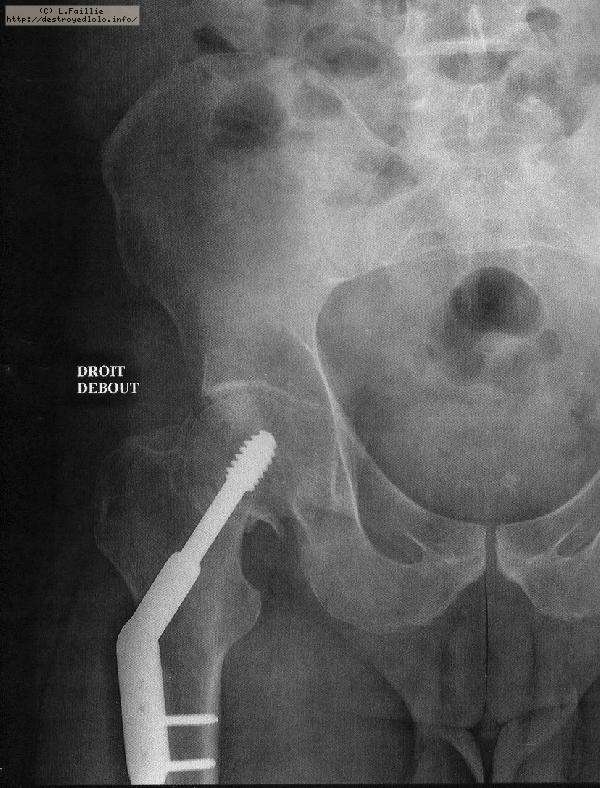

La saison est finie : fracture du col du fémur :(

Pompier, hôpital, 3 mois alités ...